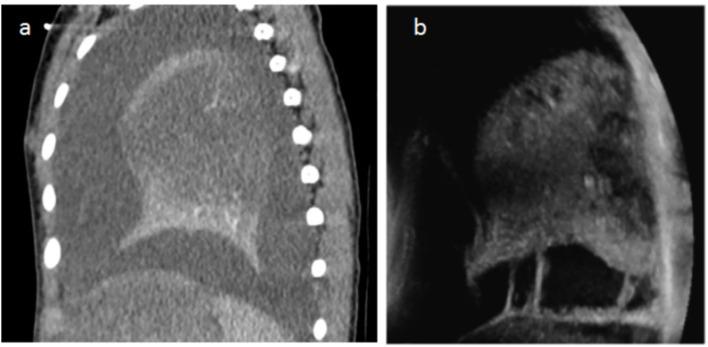

儿童坏死性肺炎:胸部计算机断层扫描与肺部超声检查的对比

The utilization of contrast-enhanced computed tomography (CT) of the chest for the diagnosis of necrotizing pneumonia (NP), a complication of community-acquired pneumonia, is controversial because of the inherent ionizing radiation involved. Over the past few years, the growing availability of bedside Lung Ultrasound (LUS) devices has led to increased use of this nonionizing imaging method for diagnosing thoracic pathology, including pneumonia.

OBJECTIVE

The objectives of this study were as follows: first, to compare the performance of LUS vs. CT in the identification of certain radiological signs of NP, and second, to determine whether LUS could replace CT in the diagnosis of NP.

Pleural effusions were demonstrated almost systematically (100% on CT vs. 95.8% on LUS). Visualization of septations in pleural effusions was clearly superior on LUS (20.4% on CT vs 62.5% on LUS). Concerning the detection of necrosis, we observed a strong correlation between LUS and the gold-standard CT (95.8% on LUS vs. 93.7% on CT). Parenchymal cavities were more easily detected on CT than on LUS (79.1 vs. 35.4%).

CONCLUSION

LUS has shown to be as effective as CT in the diagnosis of NP. The use of CT in patients with NP could be limited to the detection of complications such as bronchopleural fistulae in unfavorably evolving diseases.